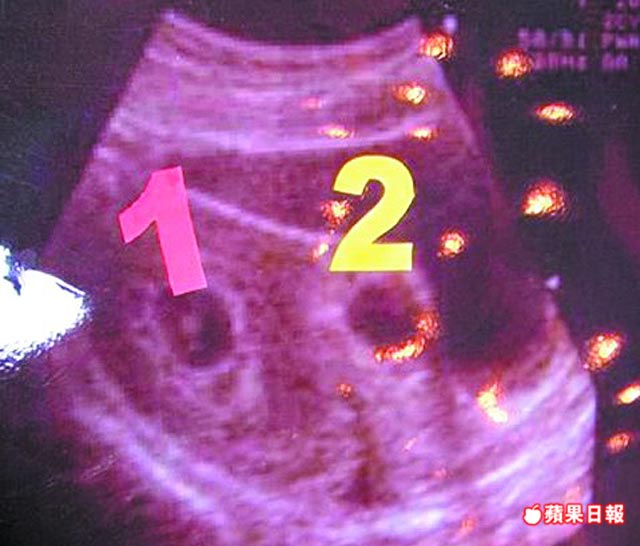

圖為超音波檢查,1指在子宮內著床的胚胎,2是跑到傷口著床的胚胎。

【高麗玲╱台北報導】一名婦人懷了雙胞胎,卻是複合性懷孕,亦即一個胚胎正常在子宮內孕育,另一胚胎卻不當著床於上胎剖腹產傷口上,隨著胚胎長大,隨時可能撐破傷口、引發大出血,危及母體性命,林口長庚醫院創新使用子宮鏡,經陰道取出此不當著床胚胎,成功保住另一個正常胚胎與母親性命。

此個案報告已獲美國《生育與不孕期刊》刊登,報告上指此手術方法是醫界首例。婦產科醫師蔡鋒博表示,這名31歲婦人,經人工受孕懷雙胞胎,但妊娠第6周時,發現有一個胚胎不當著床於剖腹產傷口上,因此轉診。